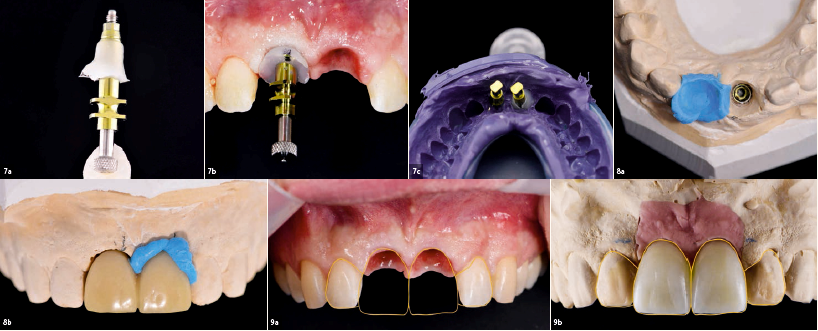

Εικ. 7A-c

Αποτυπώματα των εμφυτευμάτων στην περιοχή των 11 και 21 με εξατομικευμένο και κλασικό άξονα αποτύπωσης και το εκμαγείο που κατασκευάστηκε με βάση αυτά τα αποτυπώματα.

Εικ. 8a&b

Εκμαγείο εμφυτευμάτων. Η βασική περιοχή στην θέση του 21 τροποποιήθηκε και το προφίλ

Eικ. 9a&9b

Aνάλυση και σχεδιασμός με την χρήση της μεθόδου ψηφιακής σχεδίασης χαμόγελου